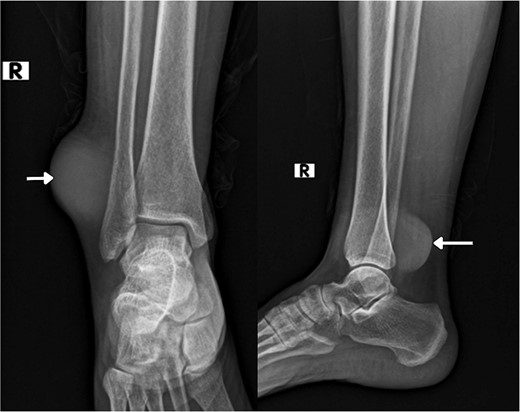

On imaging, an ankle X-ray showed an oval soft tissue mass subcutaneously at the level of the distal fibula (Fig. 2). The MRI showed about 5.7 × 3 × 5 cm of well-defined soft tissue mass within the distal lateral compartment of the lower leg, which seems locally invasive, abutting the fibular cortex, but without evidence of fibular cortical invasion (Supplementary Fig. 1). Moreover, a whole-body CT confirmed the absence of metastasis. CRP, ESR, LFT, and KFT were all within the normal range, and her bone profile was normal for her age. However, hemoglobin levels were slightly decreased (10.5 g/dl). An incisional biopsy showed features consistent with UPS. Therefore, the decision was to proceed with wide tumor resection and radiotherapy sessions.